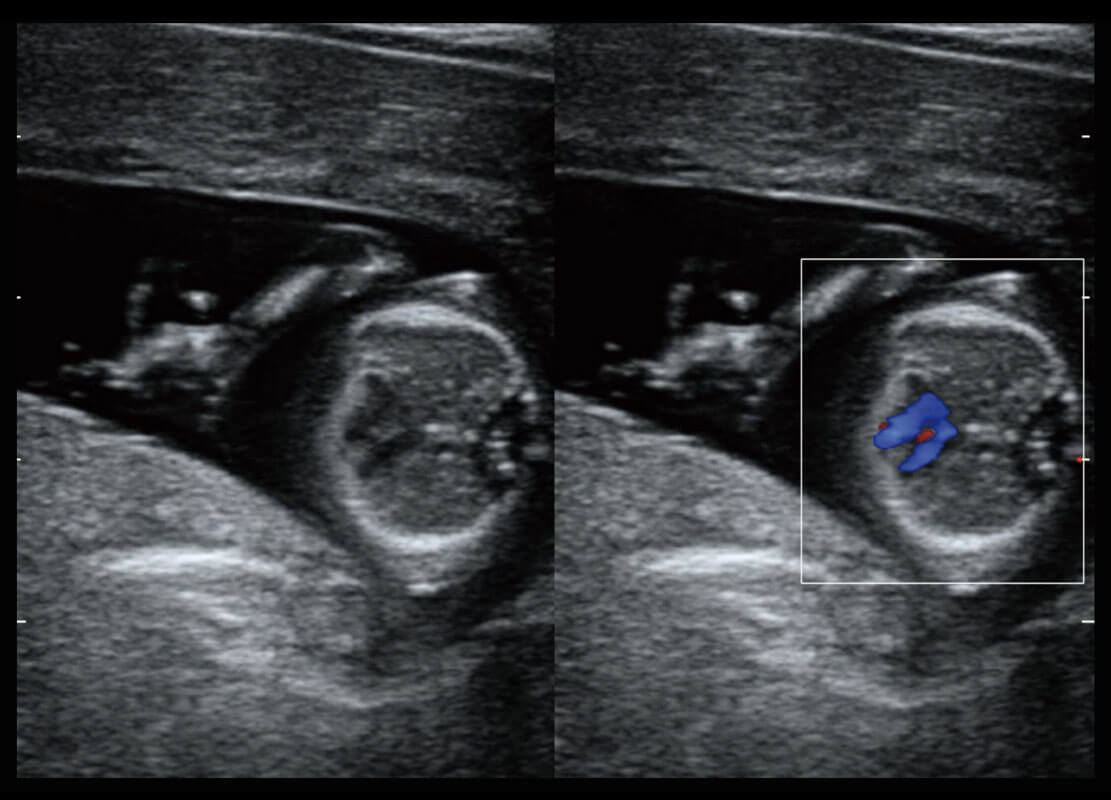

P60在胎儿早孕期超声筛查中为您带来优异的图像质量。

早孕-胎心

胎儿体循环